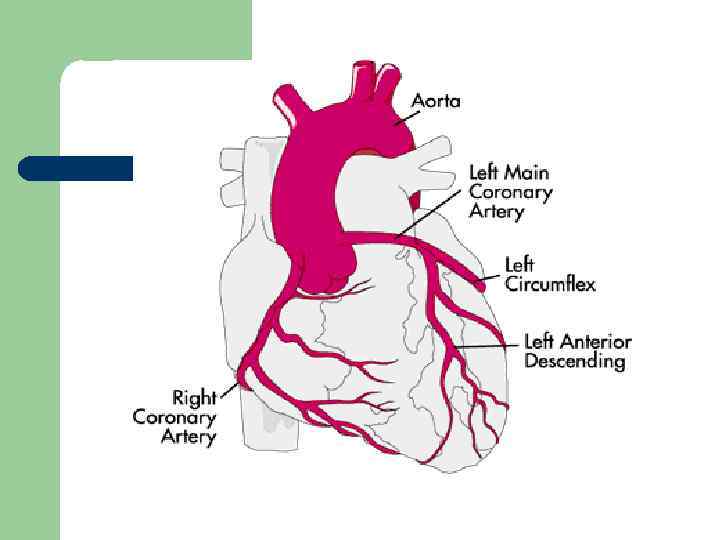

Хиругические методы лечения ИБС l l АКШ: при стенозе ствола ЛКА более чем на 50% или устьевых стенозах ПНА и ОА, при проксимальных стенозах 3 -х основных артерий, при одно- или двухсосудистом поражении с тяжёлым проксимальным стенозом ПНА, при многососудистом поражении с дисфункцией ЛЖ и/или СД. ТБКА (ЧТКА)